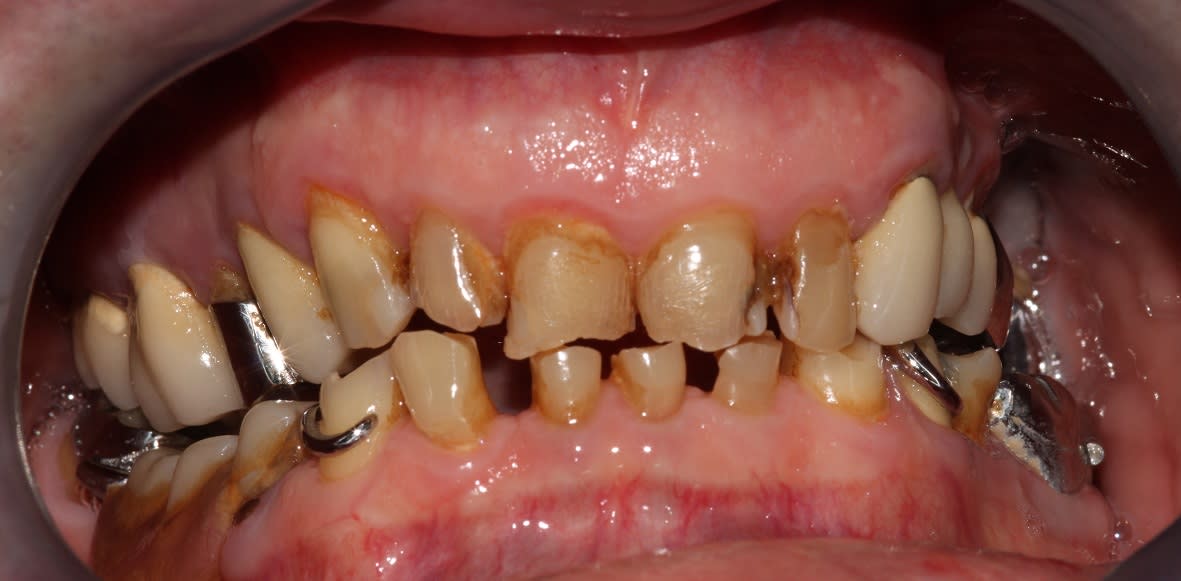

En bouche.

Le sourire est volontairement forcé, je voulais lui éviter les écarteurs.

Il avait l'air de vouloir fermer les diastèmes en bas, on verra si je rajoute quatre céramiques supplémentaires, pas d'obligation.

Petite retouche des bords libres à prévoir je pense, le jour du contrôle.